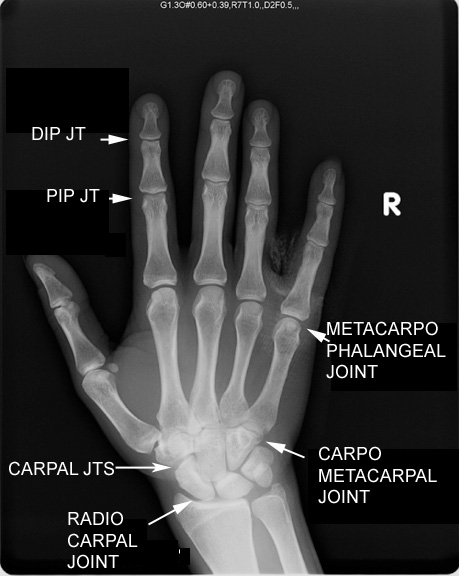

Identify the joints seen. Click the image for labeling.